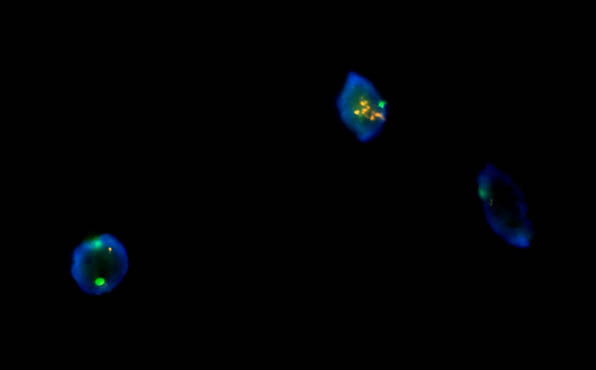

FISH荧光原位杂交产品目前在国内主要有三大领域:实体瘤、血液病和产前/流产诊断。实体瘤和血液病在医院开展FISH检测较多,与靶向药物治疗相关的一些探针观察,如乳腺癌HER-2等。产前/流产诊断,主要是染色体数目异常或结构异常。如此次北京某公司需要的荧光显微镜对试剂FISH样品进行检测

明美北京区域工程师推荐了科研级荧光显微镜MF43-N,采用优良的无限远光学系统,6孔转盘式荧光模块设计,荧光激发块更换拆除方便,可自主方便更换想要的荧光激发块。

此次,工程师推荐的全套FISH荧光显微镜整套方案包含成像软件和相机,成像清晰,操作简便,检测快速,24小时内出结果,且结果易观察,并且重复性好,空间定位准确。标本来源丰富:间期细胞、分裂中期细胞、分化或者未分化细胞以及死亡或者存活的细胞都可以被检测